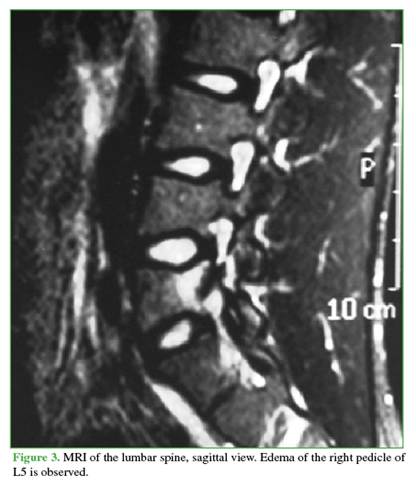

Anteroposterior, lateral, and oblique radiographs of the lumbar spine showed sclerosis of the right pedicle and left-sided spondylolysis at the level of the fifth lumbar vertebra. CT scan revealed, in addition to the findings mentioned above, a discontinuity in the right pedicle, with sclerotic and hypertrophic margins (Figures 1 and 2). Magnetic resonance imaging demonstrated edema in the lumbar pedicle (Figures 3 and 4).

A common feature of pediculolysis is sclerosis of the pedicle, although it remains unclear whether this represents an adaptive phenomenon prior to the fracture or a consequence of it.9 This unilateral sclerosis gives the vertebra an asymmetric appearance on radiological imaging. Computed tomography (CT) undoubtedly allows for better assessment of the lesion, differential diagnosis, monitoring of progression, and, in some cases, therapeutic planning. Characteristic CT findings include a radiolucent line of discontinuity with sclerotic and hypertrophic margins.4 Magnetic resonance imaging (MRI) has high sensitivity for diagnosing these lesions. While it may or may not reveal the fracture line at the pedicle level, it does demonstrate associated edema, which appears hypointense on T1-weighted sequences and hyperintense on T2-weighted sequences.3,4